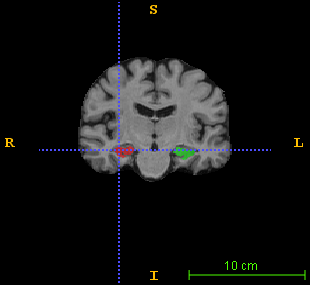

A validation study has been conducted on the brain MRI data drawn from the Alzheimer’s Disease Neuroimaging Initiative database (http://adni.loni.usc.edu). As a pilot study, 100 brain images were randomly picked: 34 healthy subjects, 33 with mild cognitive impairment (MCI) and 33 AD patients, with a demographic profile presenting no statistically significant difference on age and MMSE score from the whole database (pβˆ’v​a​l​u​e>0.1π‘π‘£π‘Žπ‘™π‘’π‘’0.1p-value>0.1). All images were bias-corrected and linearly aligned in the widely-used MNI152 template space. Each image also includes a reference manual segmentation of the hippocampus. A sample image superimposed with its label map is shown in Fig. 1.

Figure 1: A sample brain MR image superimposed with its hippocampus reference segmentation in (left) axial view, (middle) sagittal view, and (right) coronal view. The green and pink colored regions respectively indicate the left and right hippocampus